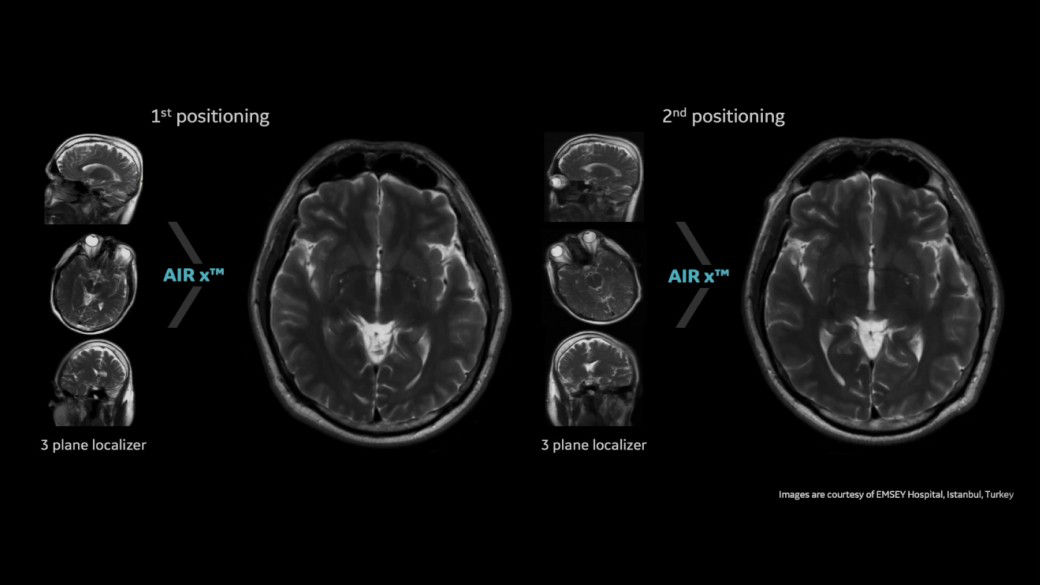

AD patients undergo repeat monitoring to measure disease progression and/or therapy effectiveness

airx-desktop

Learn more